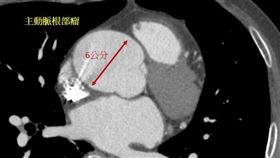

未爆彈!6.5cm「主動脈瘤」隨時索命

花蓮一名50多歲廖先生中風多年,去年因急性A型主動脈...